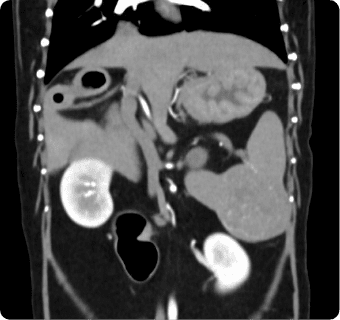

빠른 촬영속도를 통해 마취시간을 최소화 하며, 선명한 3차원 영상을 구현합니다.

종양, 전이평가, 선천적 혈관 기형 등 여러 질환의 조기 발견 및 환자상태를 평가합니다.

간, 비장, 소화기, 콩팥, 방광, 부신의 종양, 간문맥전신단락, 복강 내 실질 장기 평가, 요로결석에 의한 폐색 평가